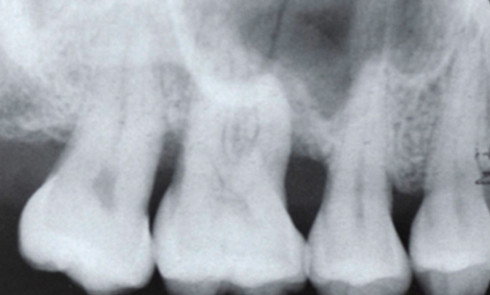

Cliniquement, la parodontite se manifeste par une atteinte du parodonte superficiel et profond : gencive œdématiée avec saignement provoqué au...